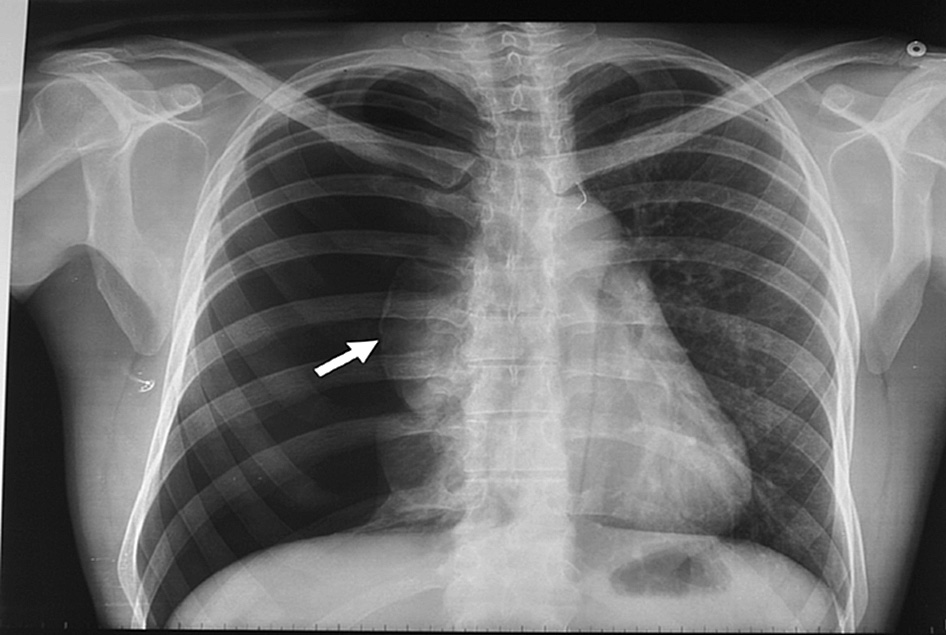

Neumotórax espontáneo: aspiración con aguja vs drenaje con tubo

05 junio 2017

El tratamiento inicial de aspiración con aguja obtiene mejore resultados inmediatos y acorta los tiempos de internación. European Respiratory Journal, abril de 2017